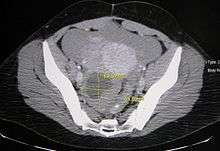

Ovarian cysts are usually diagnosed by either ultrasound, CT scan or MRI, and correlated with clinical presentation and endocrinologic tests as appropriate.

Ovarian cysts are considered large when they are over 5 cm and giant when they are over 15 cm. In children ovarian cysts reaching above the level of the umbilicus are considered giant.

Follow-up imaging in women of reproductive age for incidentally discovered simple cysts on ultrasound is not needed until 5 cm, as these are usually normal ovarian follicles. For simple cysts greater than 5 cm but less than 7 cm in premenopausal females, cysts should be followed yearly. For simple cysts greater than 7 cm, further imaging with MRI or surgical assessment is mandated as, because of their large size, these cysts cannot be reliably assessed by ultrasound alone. The primary concern for larger cysts is the potential for non-visualization of soft tissue nodularity or thickened septation at their posterior wall due to limited penetrance of the ultrasound beam. For the corpus luteum, a dominant ovulating follicle that typically appears as a cyst with circumferentially thickened walls and crenulated inner margins, follow up is not needed if the cyst is less than 3 cm in diameter. In postmenopausal patients, any simple cyst greater than 1 cm but less than 7 cm needs yearly follow-up, while those greater than 7 cm need MRI or surgical evaluation, similar to reproductive age females.[8]